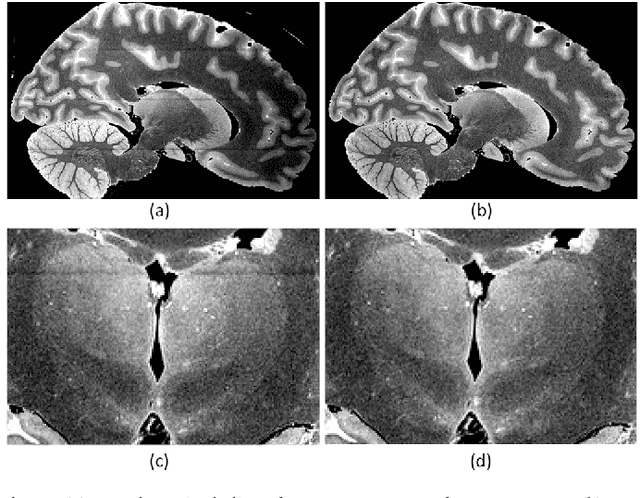

Abstract:The human thalamus is a brain structure that comprises numerous, highly specific nuclei. Since these nuclei are known to have different functions and to be connected to different areas of the cerebral cortex, it is of great interest for the neuroimaging community to study their volume, shape and connectivity in vivo with MRI. In this study, we present a probabilistic atlas of the thalamic nuclei built using ex vivo brain MRI scans and histological data, as well as the application of the atlas to in vivo MRI segmentation. The atlas was built using manual delineation of 26 thalamic nuclei on the serial histology of 12 whole thalami from six autopsy samples, combined with manual segmentations of the whole thalamus and surrounding structures (caudate, putamen, hippocampus, etc.) made on in vivo brain MR data from 39 subjects. The 3D structure of the histological data and corresponding manual segmentations was recovered using the ex vivo MRI as reference frame, and stacks of blockface photographs acquired during the sectioning as intermediate target. The atlas, which was encoded as an adaptive tetrahedral mesh, shows a good agreement with with previous histological studies of the thalamus in terms of volumes of representative nuclei. When applied to segmentation of in vivo scans using Bayesian inference, the atlas shows excellent test-retest reliability, robustness to changes in input MRI contrast, and ability to detect differential thalamic effects in subjects with Alzheimer's disease. The probabilistic atlas and companion segmentation tool are publicly available as part of the neuroimaging package FreeSurfer.